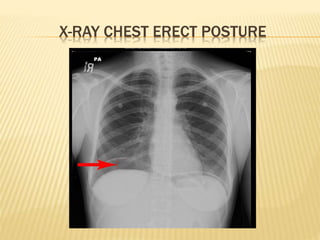

 CXR erect posture: diagnostic of GI

perforation

X-RAY CHEST ERECT POSTURE

11. INVESTIGATIONS OFUPPER GI BLEEDING  Upper GI endoscopy  Contrast studies  CXR erect posture: diagnostic of GI perforation